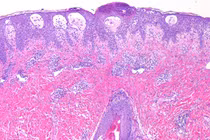

Hội chứng Stevens-Johnson và hoại tử thượng bì nhiễm độc là những phản ứng do thuốc ít gặp nhưng rất nặng, đe dọa tính mạng của người bệnh. Tần suất của bệnh trong dân số chỉ khoảng 2/1.000.000 người nhưng tỷ lệ tử vong của bệnh rất cao, tới 5-30%.